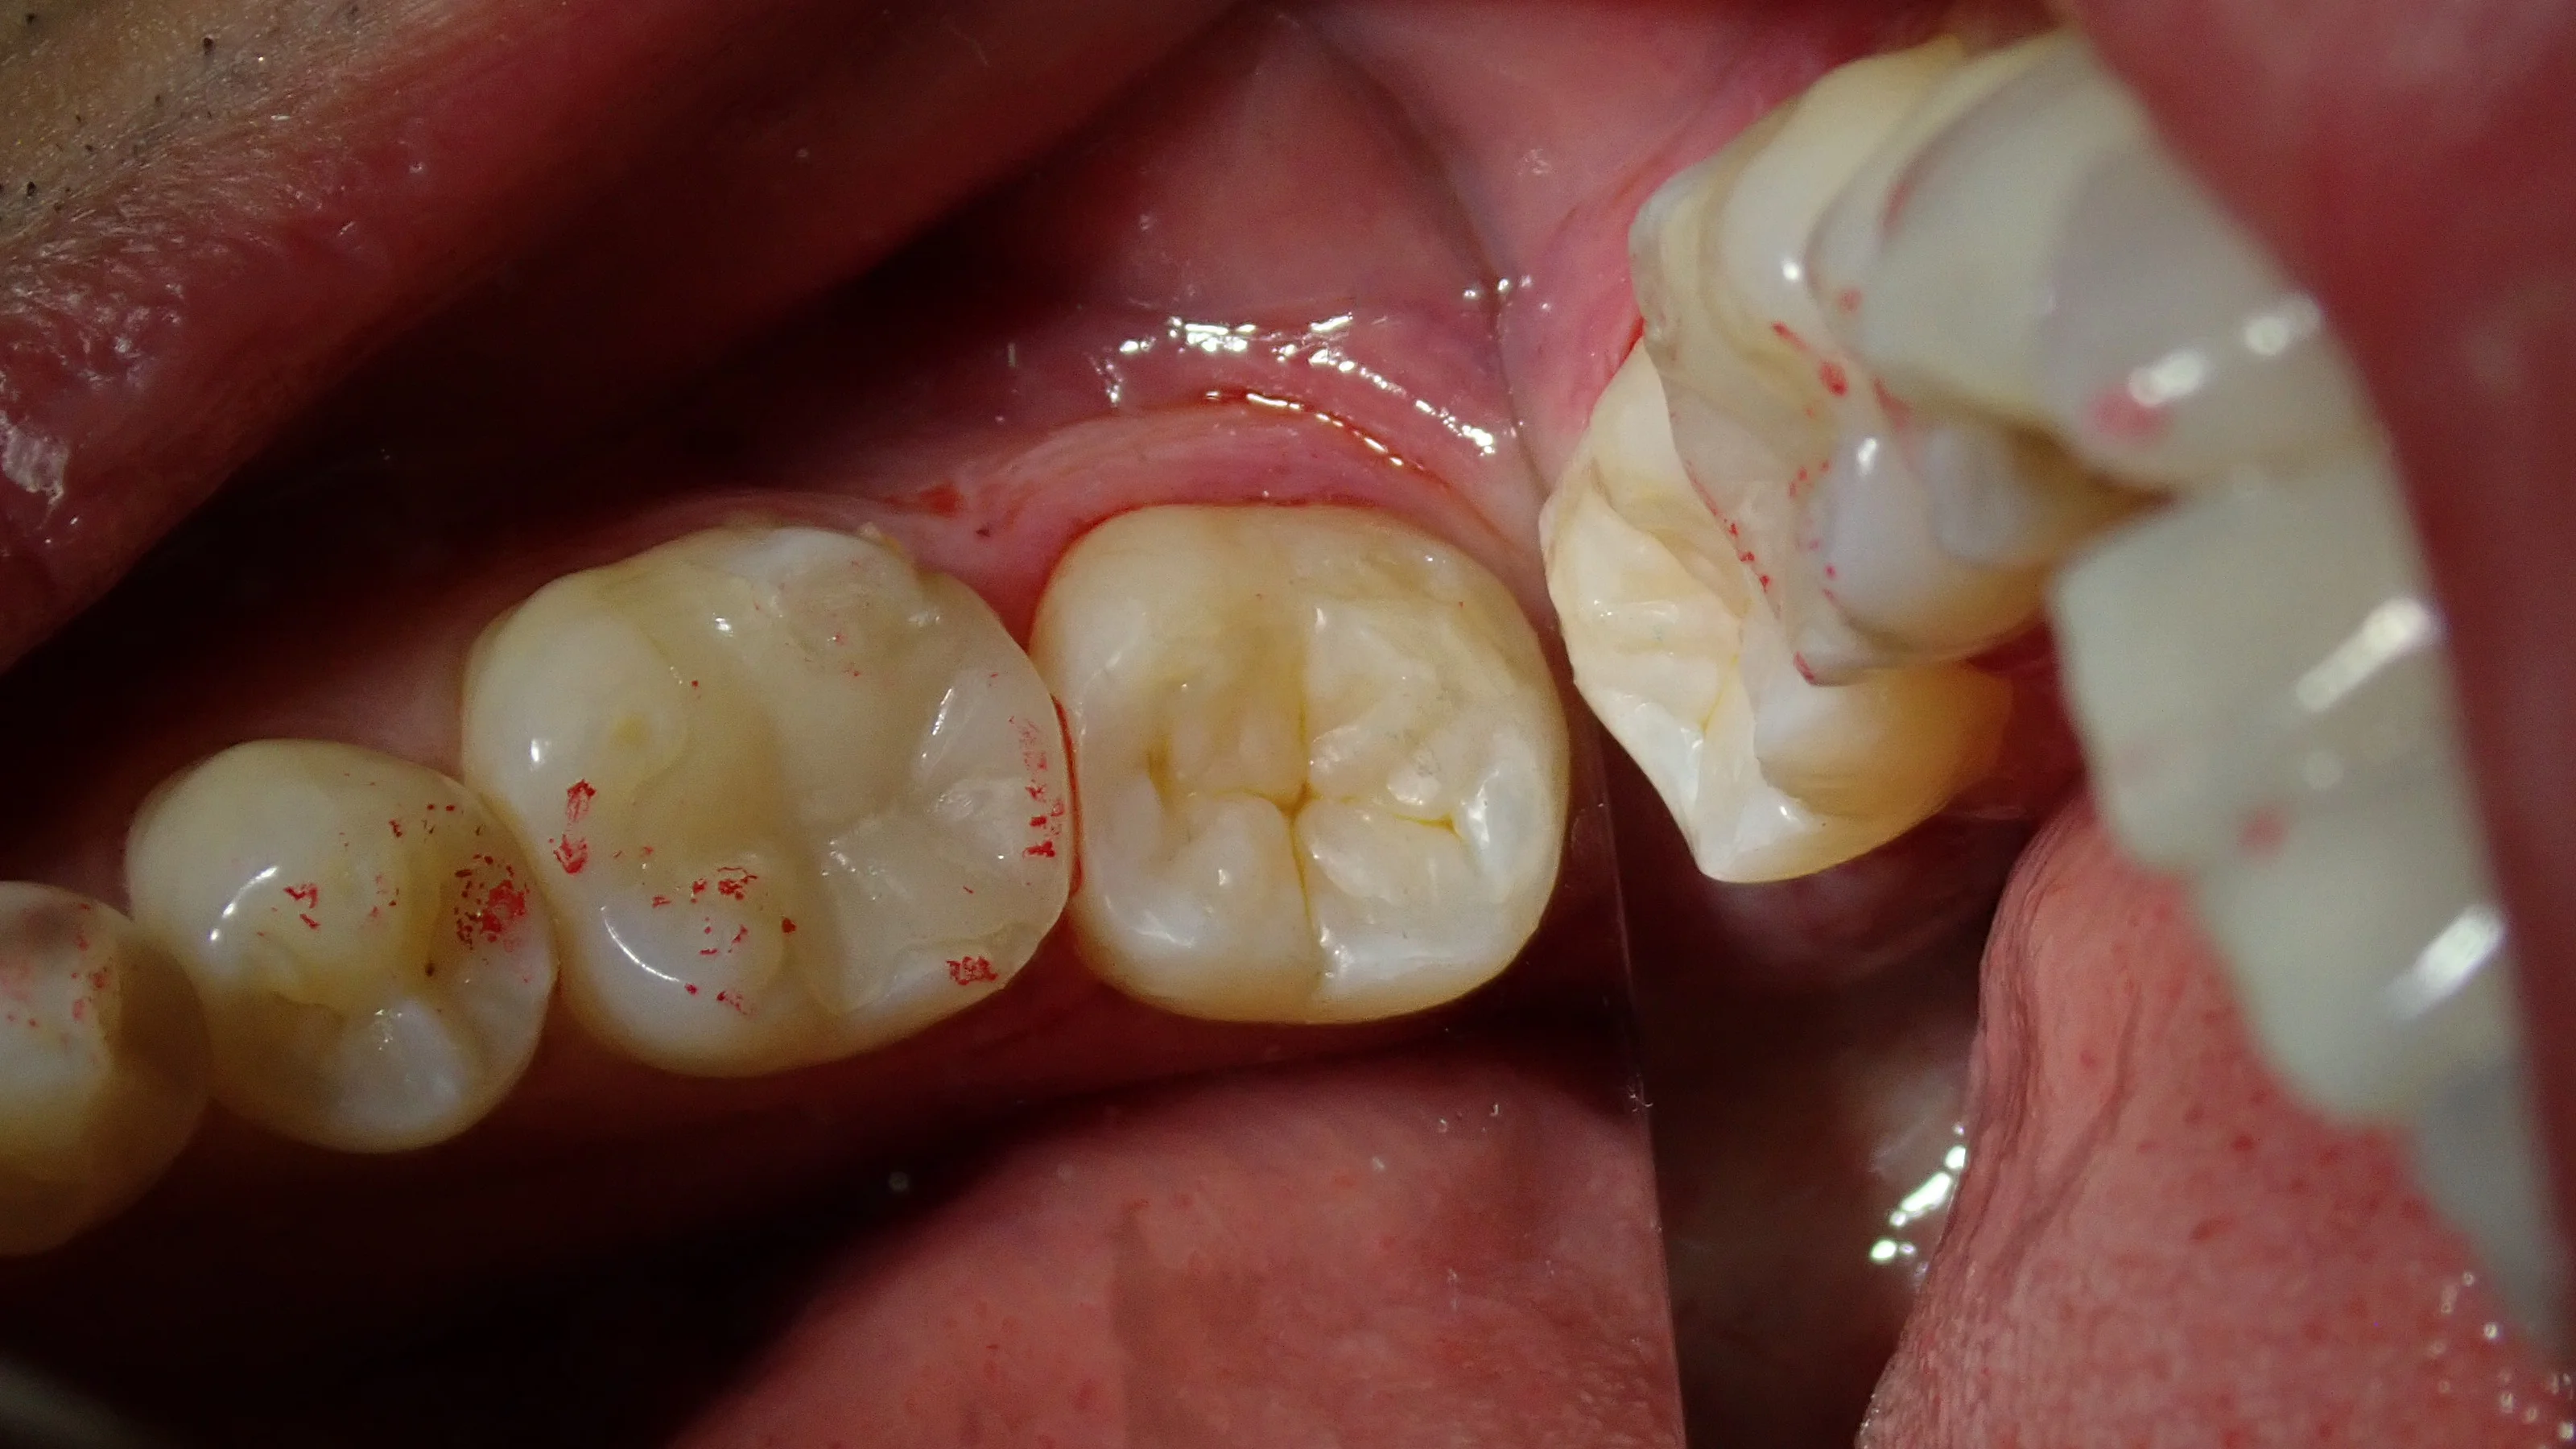

ちなみに、虫歯を取りきった後の写真がこちらです。

左下奥の白い詰め物|坂寄歯科医院(取手市藤代) - 画像2

結構神経ギリギリになりました。

歯に色がついている所が残っていますが、ここは十分な硬さもあり、虫歯に汚染されている部分ではありません。

このまま詰めてしまっても全く問題はありません。

というより、ここまで取りきると神経が出てしまいかねないので、むしろここは取るとマズイ所ですね。